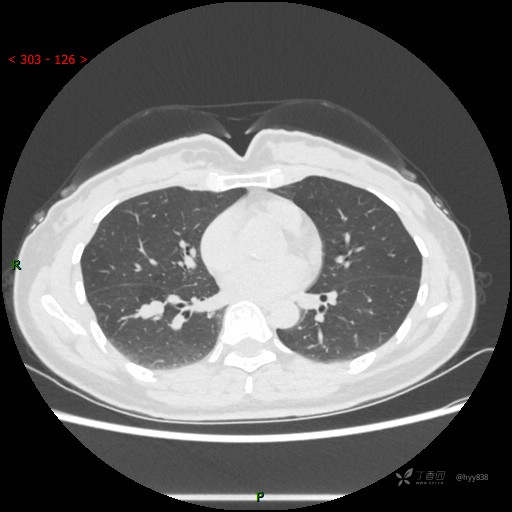

辅助检查:CT

增强动脉期